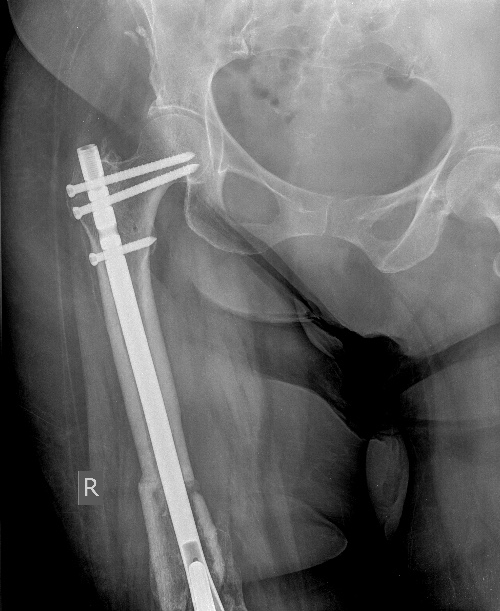

[Ortho] Перипротезный перелом бедра у ребёнка

Оптимальное решение - закрытый остеосинтез интерамедуллярным стержнем с

удлинением ножки эндопротеза. Пример в приложении. Делает такие стержни

предприятие ЦИТО.

Имя     : Бедро AP.0002.jpg